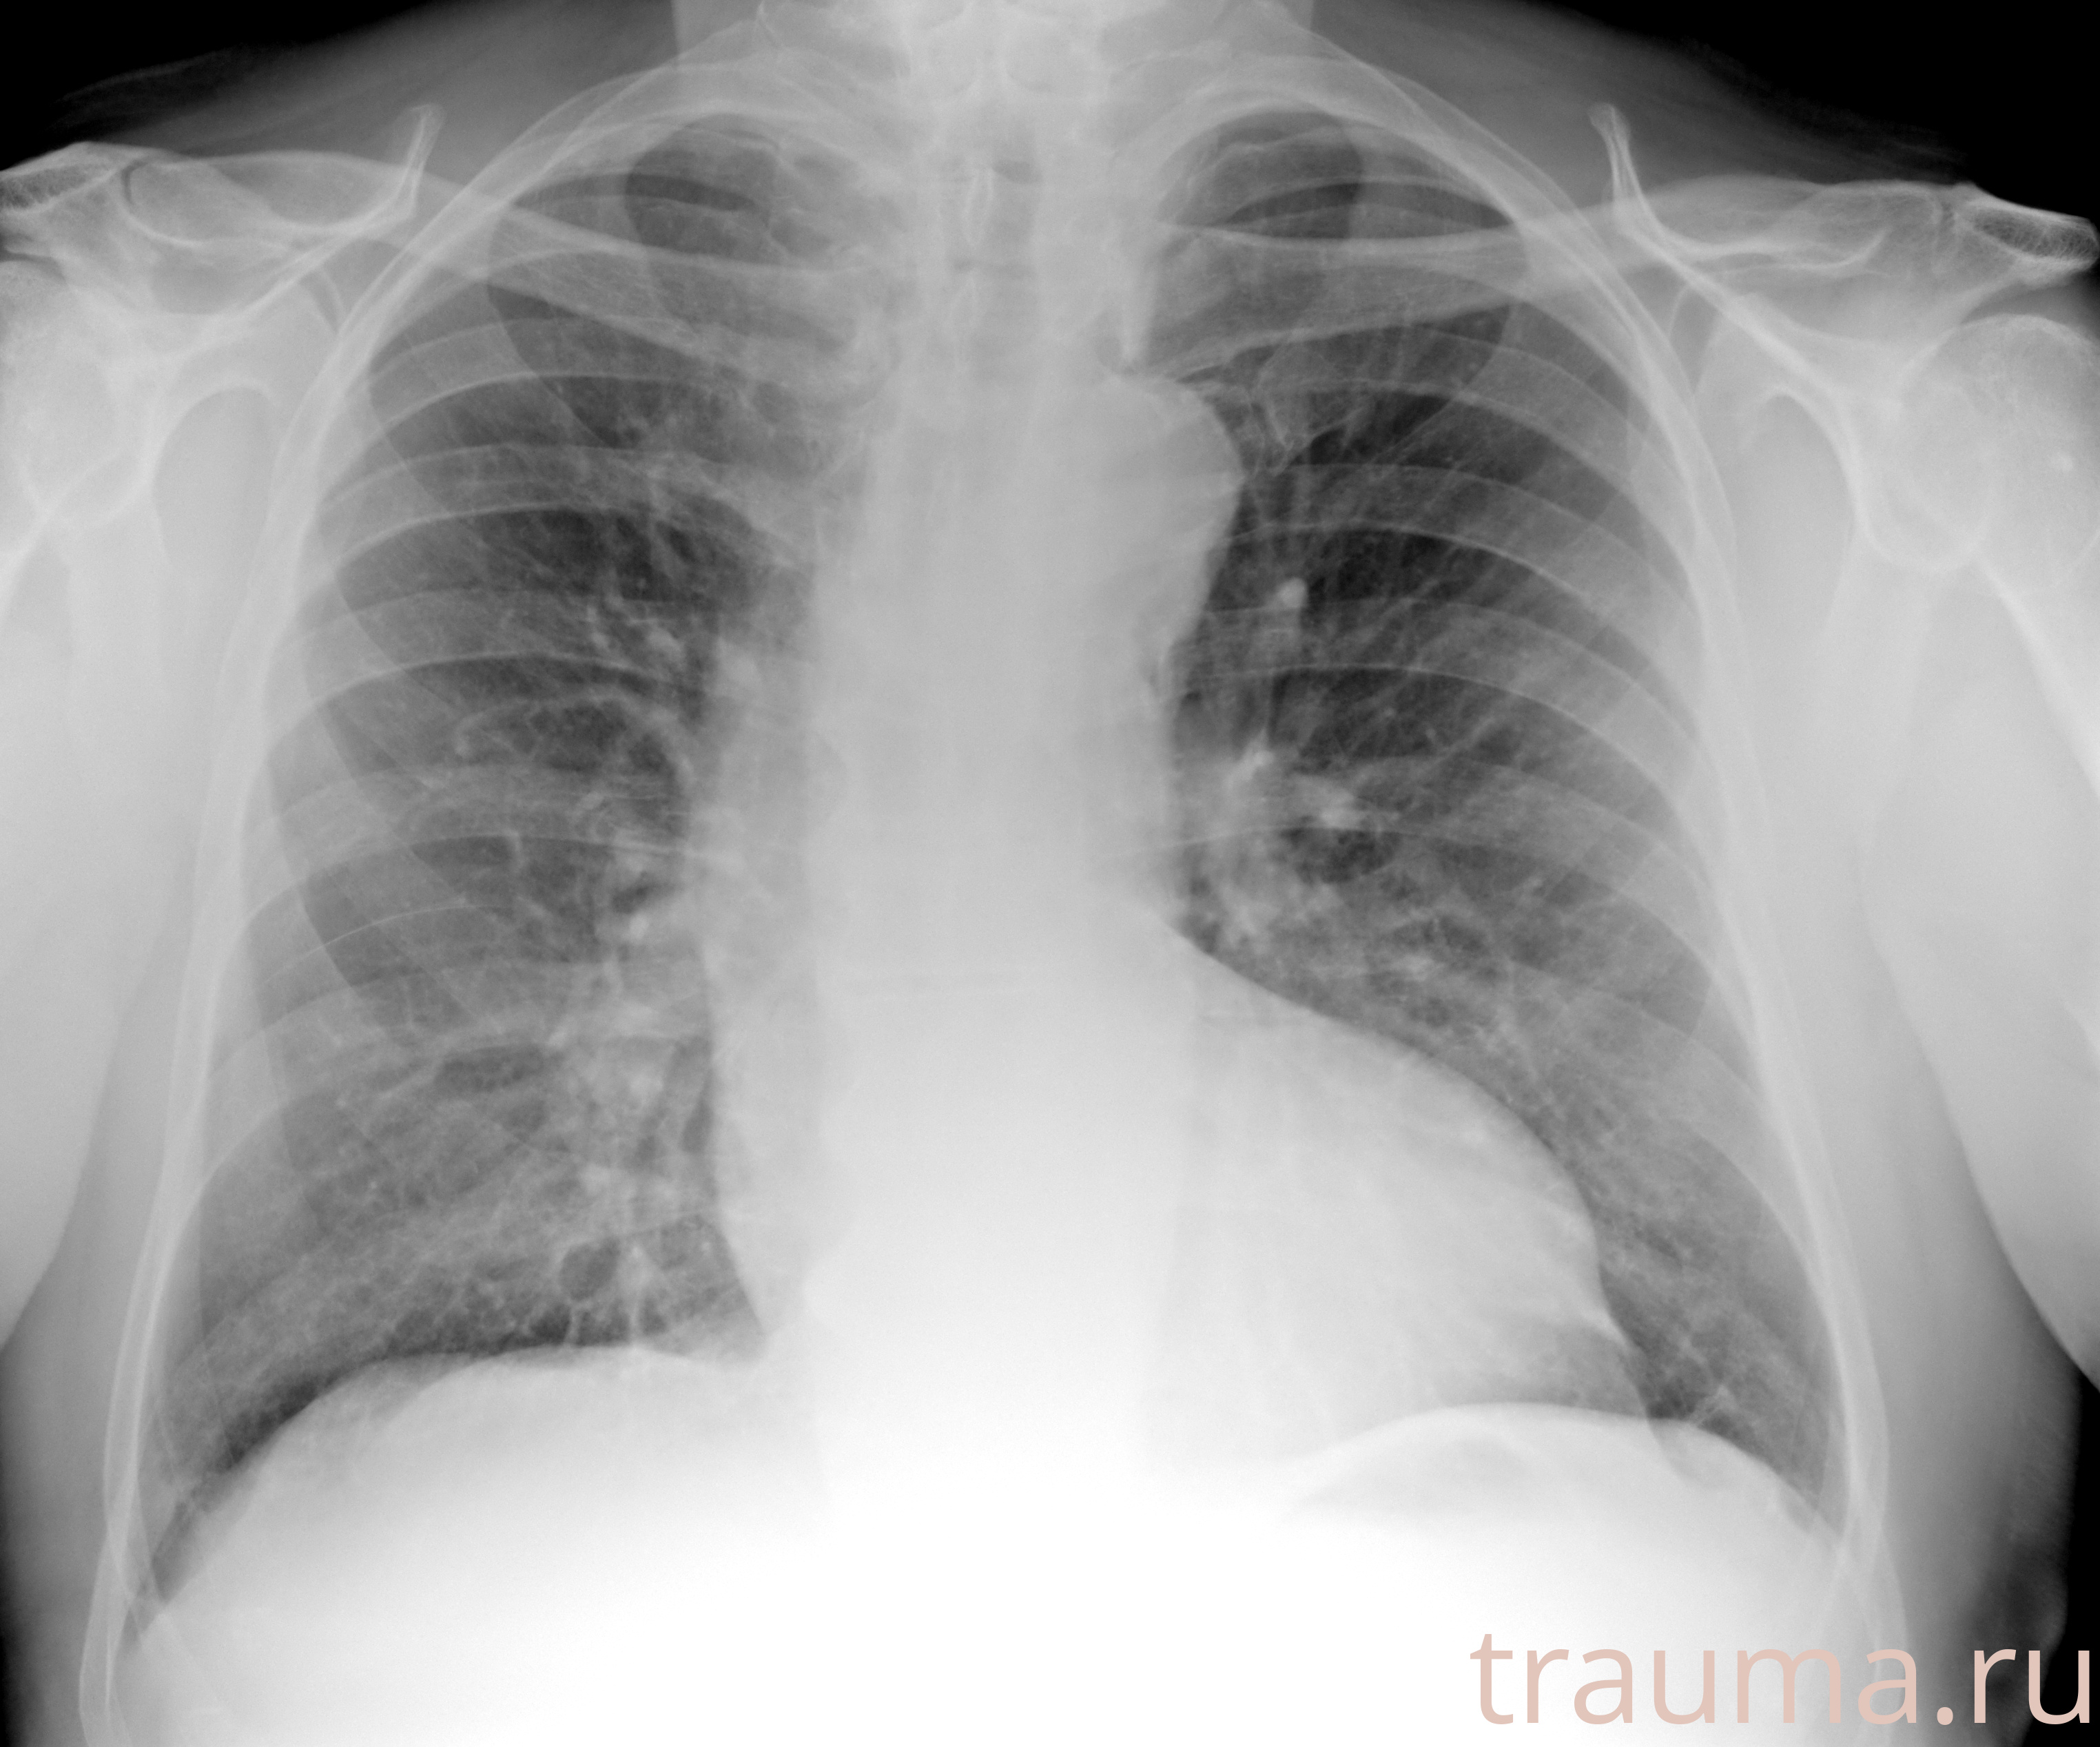

Рентгенограммы

Рентген на дому: по вашему адресу приезжает врач-рентгенолог, травматолог-ортопед с мобильным рентгеновским аппаратом, проводит диагностику травмы или заболевания, делает необходимые рентгенограммы, дает рекомендации по дальнейшему лечению. Получить качественные снимки в домашних условиях возможно благодаря уникальной методике, разработанной МосРентген Центром для института  Склифосовского

Яркость: 1   Контраст: 1   Инвертировать: 0 Увеличение: 1

Перетаскивайте мышь вверх/вниз для контраста, влево/право для яркости. Прокрутка колесом изменяет масштаб. Нажмите Сбросить для возврата к исходному изображению. При увеличении держите мышь в той области, которую хотите рассмотреть.